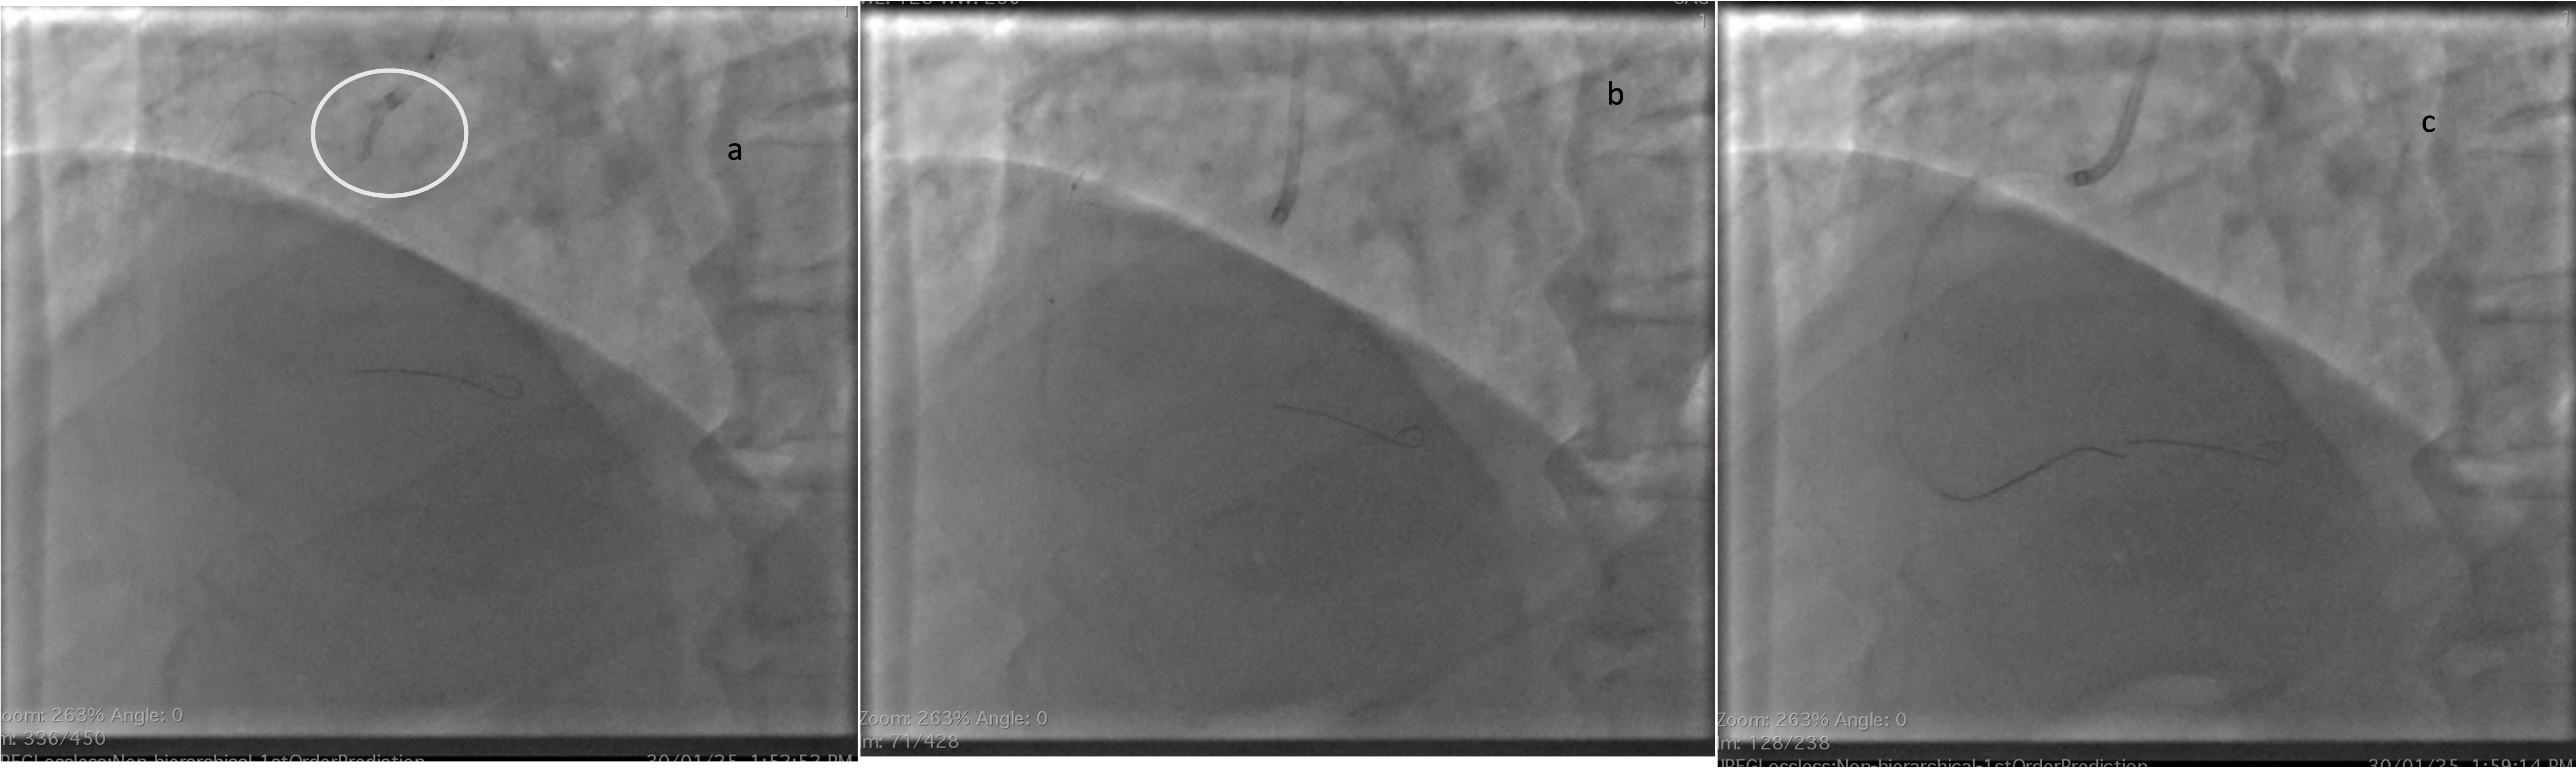

Immediately a 6 French JR 3.5 catheter was taken and right coronary artery ostium was engaged. Then a work horse wire was parked distally in posterolateral vein branch. Then a 2.75 x 23 mm Drug eluting stent was deployed across the lesion (Figure 4a). After deployment angiogram showed haziness at the distal edge of the stent. Nitroglycerine, nicorandil and tirofiban injections were given and check angiogram showed no improvement in the distal edge haziness (figure 4b). In view of possible dissection it was decided to cover the distal edge with one more DES. While passing the second DES due to poor catheter support manipulation led to degloving of the stent from balloon (figure 5a). As the wire was still in position we tried to pass the same stent balloon through the degloved stent and tried to remove en masse. However balloon. Couldn¡¯t be passed through the stent (Figure 5b). We then tried a 1 x 8 mm balloon to pass through the stent and inflated the balloon beyond the stent and tried to pull the stent into guide. However the stent could be negotiated till the guide tip but couldn¡¯t enter the guide (Figure 5c). As further manipulations may risk the stent being lost in systemic circulation with risk of embolization, we have decided to crush the stent with another stent. So a 3 x 33 mm DES was positioned over a newly placed wire and deployed crushing the previously degloved stent. Check angiogram showed good flow with no visible dissections at the proximal stent. (Figure 6)